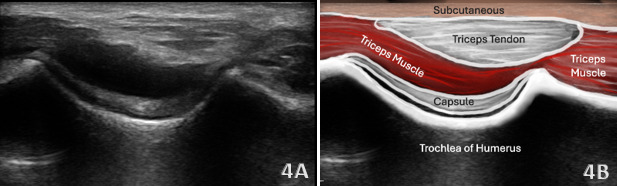

Normal Sonographic Appearance

Typically, the triceps tendon will be viewed in both the long axis (LAX) and the short axis (SAX). In the LAX view one should start distally to visualize the hyperechoic reflection of the humeral cortex. Proximal to the cortex one should visualize the hypoechoic medial triceps muscle, which is deep to the hyperechoic, fibrillar echotexture of the triceps tendon as it tapers toward the olecranon. In the SAX view, the image should be a non-uniform mixture of muscle, tendon and bone. In this view, the depression-like hyperechoic area is the olecranon process. The triceps muscle will be viewed as hypoechoic tissue, while the triceps tendon will be more hyperechoic in appearance. Maneuvering the transducer will help reduce anisotropy in this region.